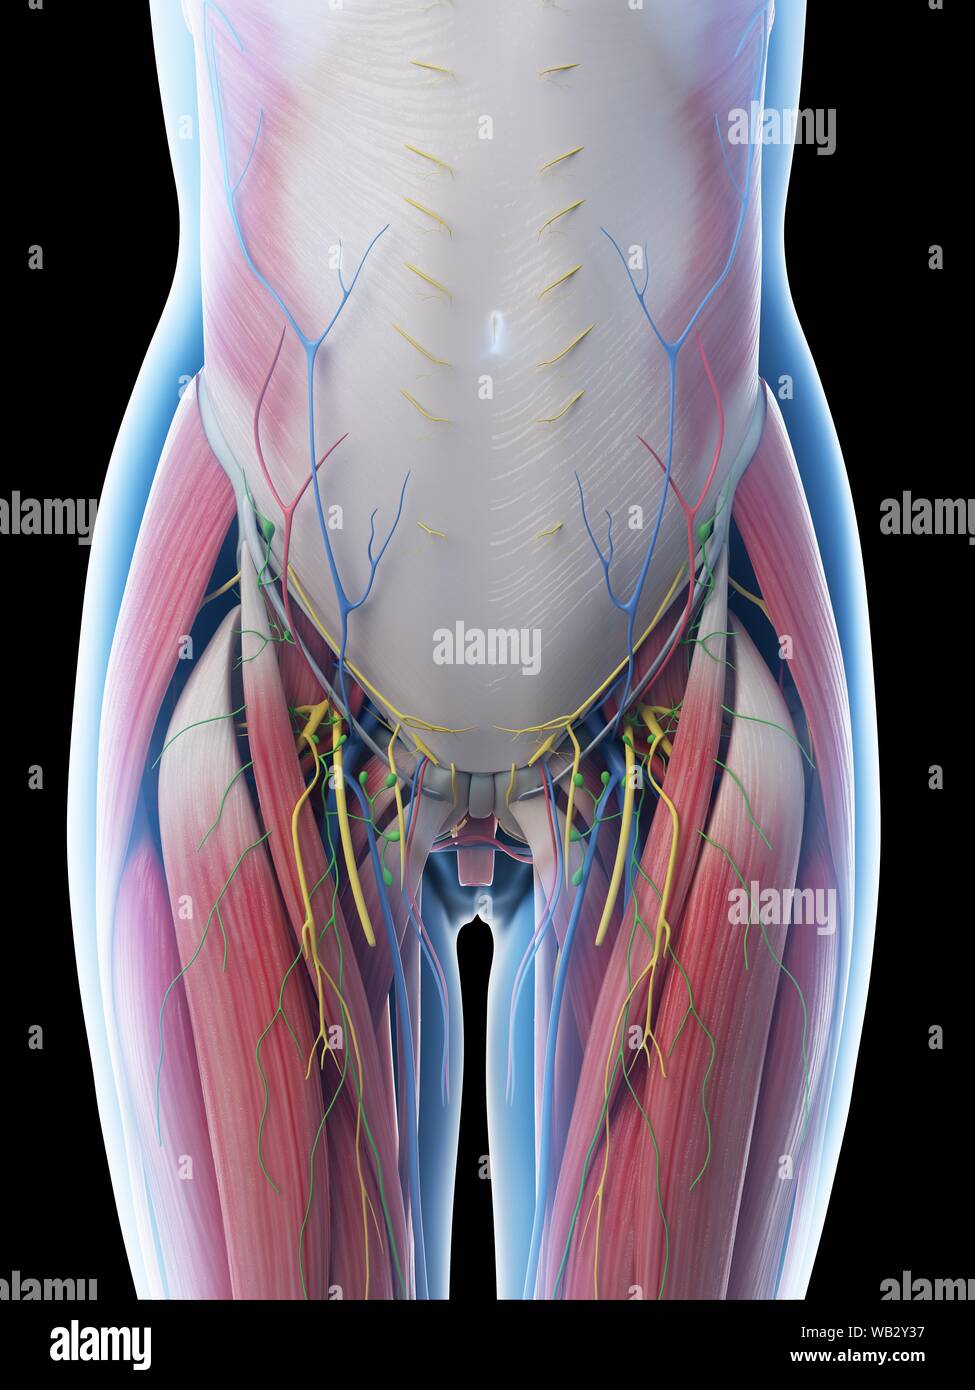

Anatomie de l'abdomen femelle, illustration de l'ordinateur. Banque D'Imageshttps://www.alamyimages.fr/image-license-details/?v=1https://www.alamyimages.fr/anatomie-de-l-abdomen-femelle-illustration-de-l-ordinateur-image264981899.html

Anatomie de l'abdomen femelle, illustration de l'ordinateur. Banque D'Imageshttps://www.alamyimages.fr/image-license-details/?v=1https://www.alamyimages.fr/anatomie-de-l-abdomen-femelle-illustration-de-l-ordinateur-image264981899.htmlRFWB2Y37–Anatomie de l'abdomen femelle, illustration de l'ordinateur.